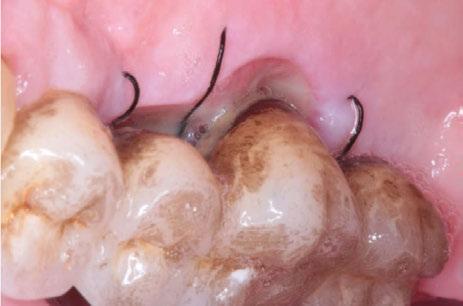

Figura 1. Caso clínico 1. Situación clínica basal de una paciente que presenta recesiones gingivales con pérdida de inserción interproximal en el quinto sextante. A la exploración se observa una profundidad de sondaje incompatible con salud en centro-vestibular del diente en posición de 41, presumiblemente combinado con una dehiscencia ósea.

CASO CLÍNICO 1 (FIGURAS 1-7)

Paciente de 32 años de edad que acude a la consulta preocupada por la situación de su diente en posición de 41. Le preocupa tanto a nivel de salud como a nivel estético. Además, refiere incapacidad para llevar a cabo un correcto cepillado de esa zona e hipersensibilidad dental.

A la exploración clínica presenta una recesión RT3 (23) en el diente en posición de 41. Además, carece de una banda de encía queratinizada adecuada (≥2mm) y presenta una reducción significativa de la

profundidad de vestíbulo combinada con la inserción alta y/o aberrante del frenillo labial incapacitando un correcto mantenimiento de la zona (24).